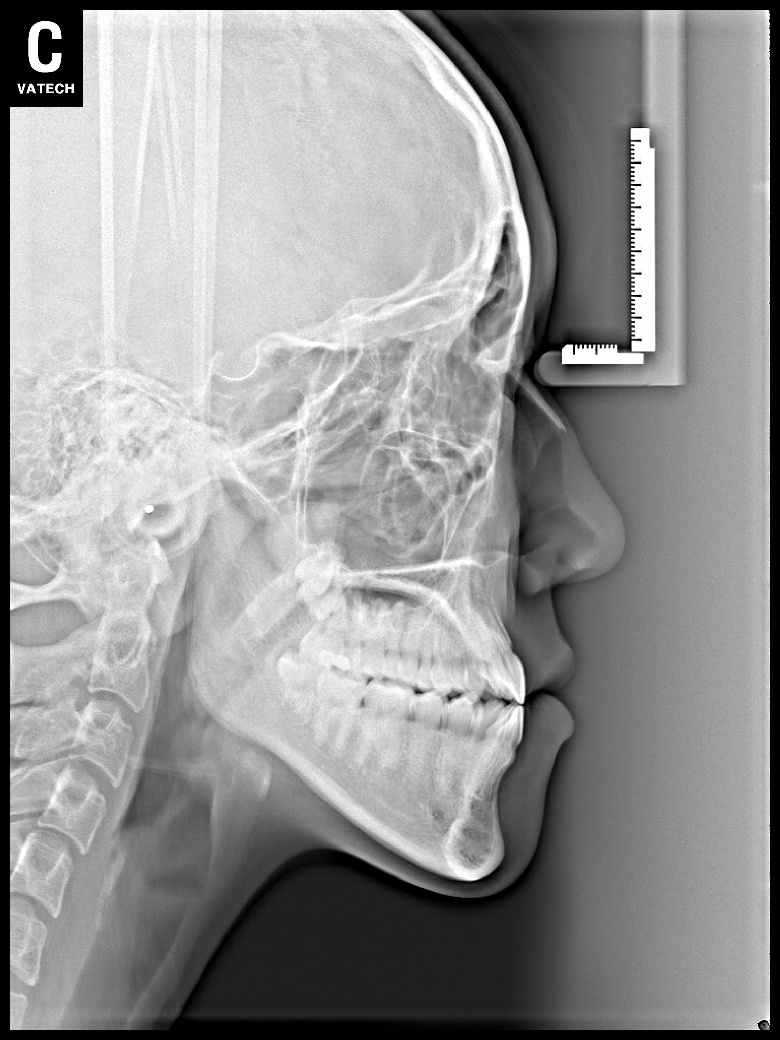

치료 후 사진입니다.